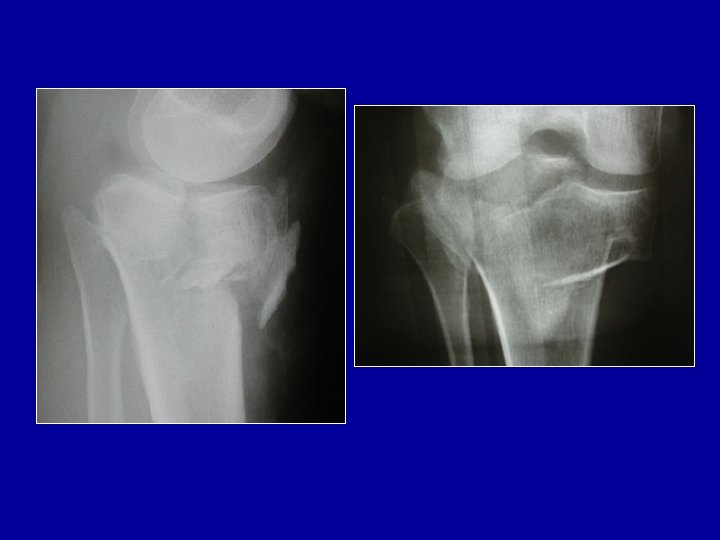

Fractures articulaires

Fractures articulaires Fracture-enfoncement du plateau tibial externe : relèvement + greffe

Fractures articulaires Fracture-séparation du plateau tibial

Fractures articulaires Fracture métaphysaire et des plateaux tibiaux